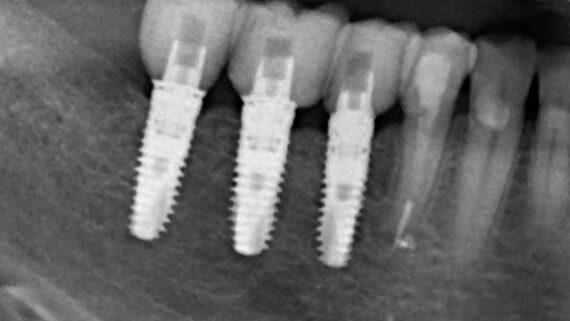

Теперь сделай контрольные снимки (обычно мы проводим ортопантомографию):

назначь пациенту необходимое постоперационное лечение и пригласи на приём через 1-2 дня.

Замечу, что в настоящее время примерно две трети остеопластических операций мы сочетаем с установкой имплантатов — и это не считая обычного сочетания имплантации с синуслифтингом. И, в принципе, получаем очень приличные результаты. И пациенты довольны — их лечение заняло меньше времени, они потратили меньше денег: